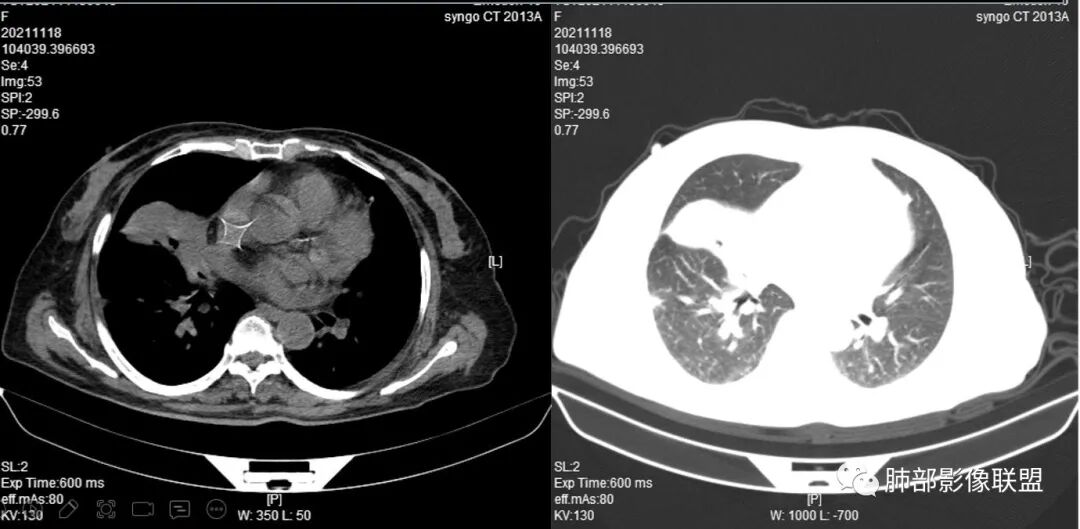

抗真菌治疗1月后复查

4.白血病化疗后,CT上出现多发结节,边缘可见晕征,病灶内可见多发坏死,右肺中叶肺动脉可见充盈缺损,右肺中叶可见融冰征,右肺中叶肺动脉侵犯栓塞伴右肺中叶肺梗死,可符合真菌感染。

血管侵袭性曲霉病是最常见的类型,其特征是真菌菌丝侵入和阻塞中小肺动脉,形成凝固性坏死、肺泡出血或出血性梗死。

6.肺曲霉病典型的CT表现是结节周围有磨玻璃样的晕征表现,或胸膜为宽基底的楔形实变。晕征表现为曲菌感染的肺结节伴梗死和凝固性坏死,周围有肺泡出血。最终可出现空泡征象,并可观察到中央坏死组织与周围肺实质分离形成空气新月征。